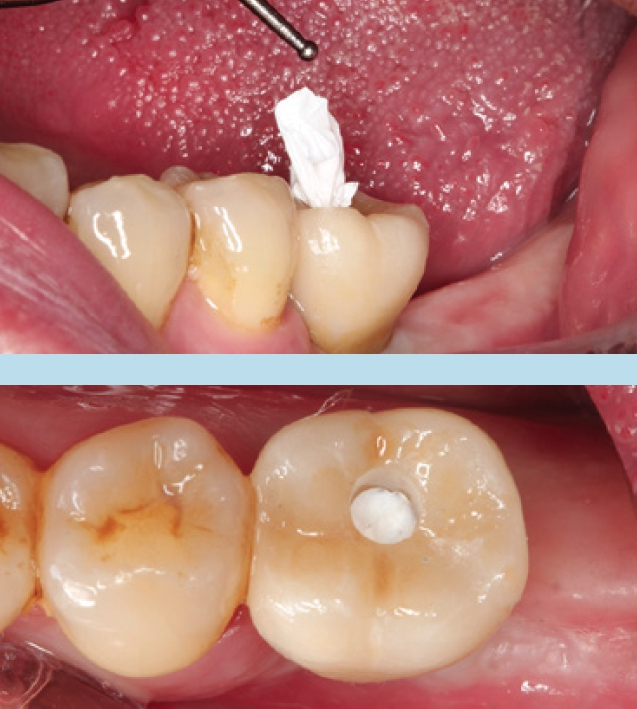

Hinsichtlich des Einsetzens punktet eher die zementierte Krone: Das Verschrauben gestaltet sich komplexer als das Einsetzen zementierbarer Kronen. Sind bei direktem Verschrauben die approximalen Kontaktpunkte nur etwas zu straff, erreicht die Ratsche das vom Hersteller vorgegebene Drehmoment bereits, bevor Kronenbasis und Implantatschulter bündig aufeinanderliegen. Da die Krone zwischen den Nachbarzähnen „klemmt“, werden diese in den nächsten Tagen und Wochen „kieferorthopädisch“ verdrängt. Dadurch kommt es zur Schraubenlockerung der Implantatkrone. Hier empfiehlt es sich, den Schraubenkanal zunächst mit Teflonband auszulegen und den Patienten nach 2 bis 4 Tagen wieder einzubestellen, um noch einmal mit definiertem Drehmoment nachzuziehen.

Direkt verschraubte Kronen und Brücken weisen technisch bedingt weitere Nachteile gegenüber zementierten Konstruktionen auf. So ist die Darstellung von approximalen oder okklusalen Vorkontakten besonders im Molarenbereich klinisch erschwert und kann ein zeitaufwendiges wiederholtes Ein- und Ausdrehen der gesamten Restauration erfordern. Schwierig ist ebenso die Umarbeitung der bereits gefügten Krone bei Mängeln in der farblichen Gestaltung bzw. bei ungenügenden approximalen Kontakten. Insbesondere die Materialkombination Titanklebebasis mit monolithischer Lithiumdisilikatkrone sei hier erwähnt. Eine Einprobe ohne Fixierung beider Komponenten macht zur Kontrolle der approximalen und okklusalen Kontaktpunkte wenig Sinn, da die Krone so nicht in die exakte Position gebracht werden kann. Ist jedoch bereits geklebt, können nachfolgende Brände im Labor nicht mehr erfolgen, da die Komposit-Klebefuge beschädigt würde. Als Kompromiss bietet sich in diesem Fall eine Einprobe der Krone mit einem kleinen Punkt Cyanoacrylat zur Fixierung auf der Klebebasis an. Diese Verbindung kann im Ultraschallbad des zahntechnischen Labors wieder kontrolliert rückgängig gemacht werden ohne die Restauration zu beschädigen.

Unabhängig, ob digital oder analog vorgegangen wird, ist bei der Einbringung der Abformpfosten bzw. Scanbodies darauf zu achten, dass diese sich nicht berühren oder die Nachbarzähne touchieren. Liegen Freilegung und Implantation zeitlich weit auseinander und wurde die Lücke nicht provisorisch versorgt, kann es zum Aufwandern der Nachbarzähne kommen (Abb. 14–17). In diesem Fall ist es notwendig, die Abformpfosten zu beschleifen oder das Aufwandern kieferorthopädisch zu behandeln.

Cave: Veränderungen an den Okklusalflächen durch provisorische Füllungen oder Kronen bei fehlendem Lückenersatz können zu Zahnbewegungen in die Lücke führen. Das Tragen eines nächtlichen Retainers in Form einer Miniplastschiene kann dies verhindern.